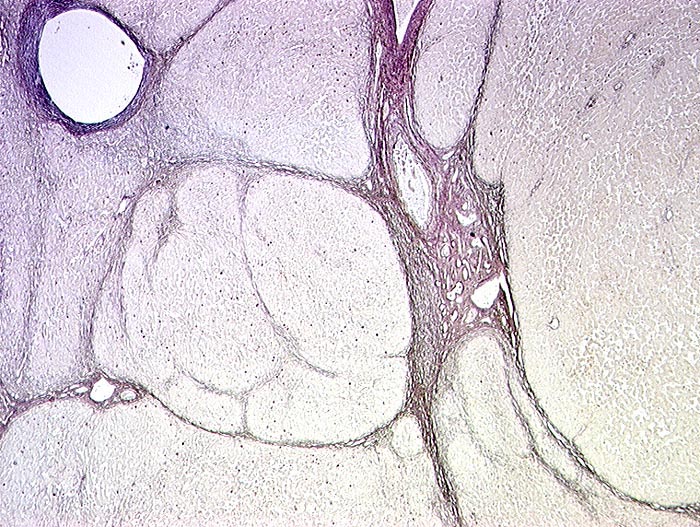

Chronische Hepatitis B

Leber

Pathologischer Befund